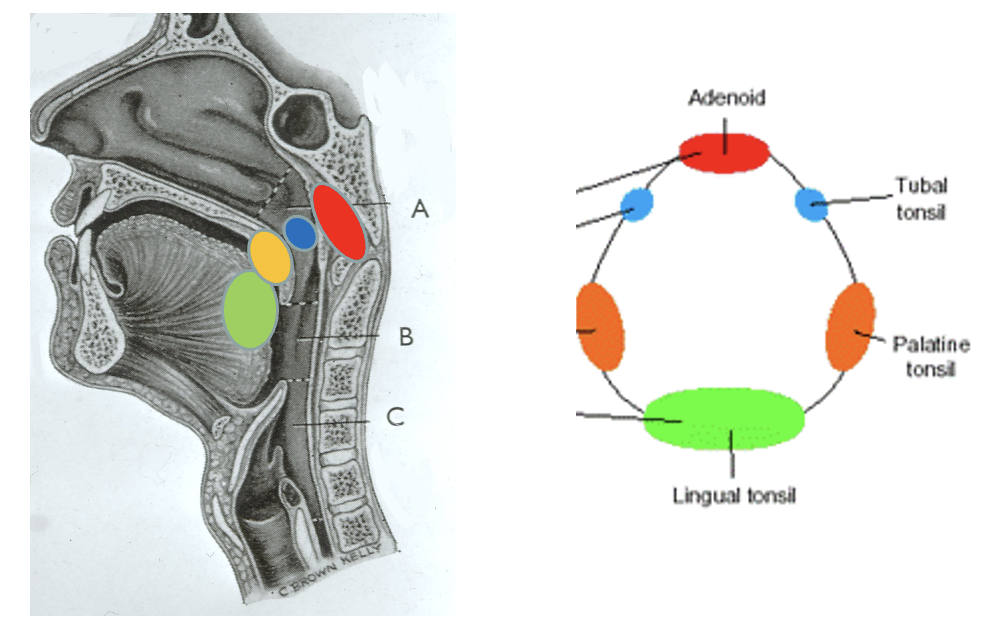

what is this diagram showing

Waldeyer’s tonsillar ring

tonsils: state the groups of tonsillar tissue

4 groups of tonsillar tissue

palatine tonsils - paired

pharyngeal tonsils/ adenoids - unpaired

lingual tonsils - paired

tubal tonsils - paired

tonsils: which two types are variable in size

pharyngeal tonsils/ adenoids

tubal tonsils